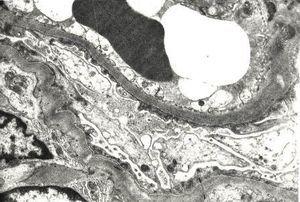

The two other groups of glomerular diseases for which the EM study was essential were the mesangiocapillary GN (MPGN) and the hereditary glomperulopathies. EM is essential for the accurate categorization of the subtypes of MPGN, as shown in Figure 2. Similarly, EM study is essential for the correct diagnosis of all cases of hereditary glomerular diseases.10 We found one case each of Alport’s syndrome (Figure 3) and tthin basement membrane disease (TBMD) in this series. It is interesting to note that TBMD typically does not cause NS, but occasional cases have been described with nephrotic range proteinuria.24 Additionally, the diagnosis of TBMD can not be based solely on morphological criteria, as many cases of Alport’s syndrome, can present with this phenotype. Genetic and pedigree analysis can resolve the differential in such cases. No family history was available of renal disease in our case and genetic testing could not be done due to non-availability of this facility.

Figure 2. Peripheral capillary loops showing numerous electron dense deposits in subendothelial location in a case of mesangiocapillary glomerulonephritis, type I.